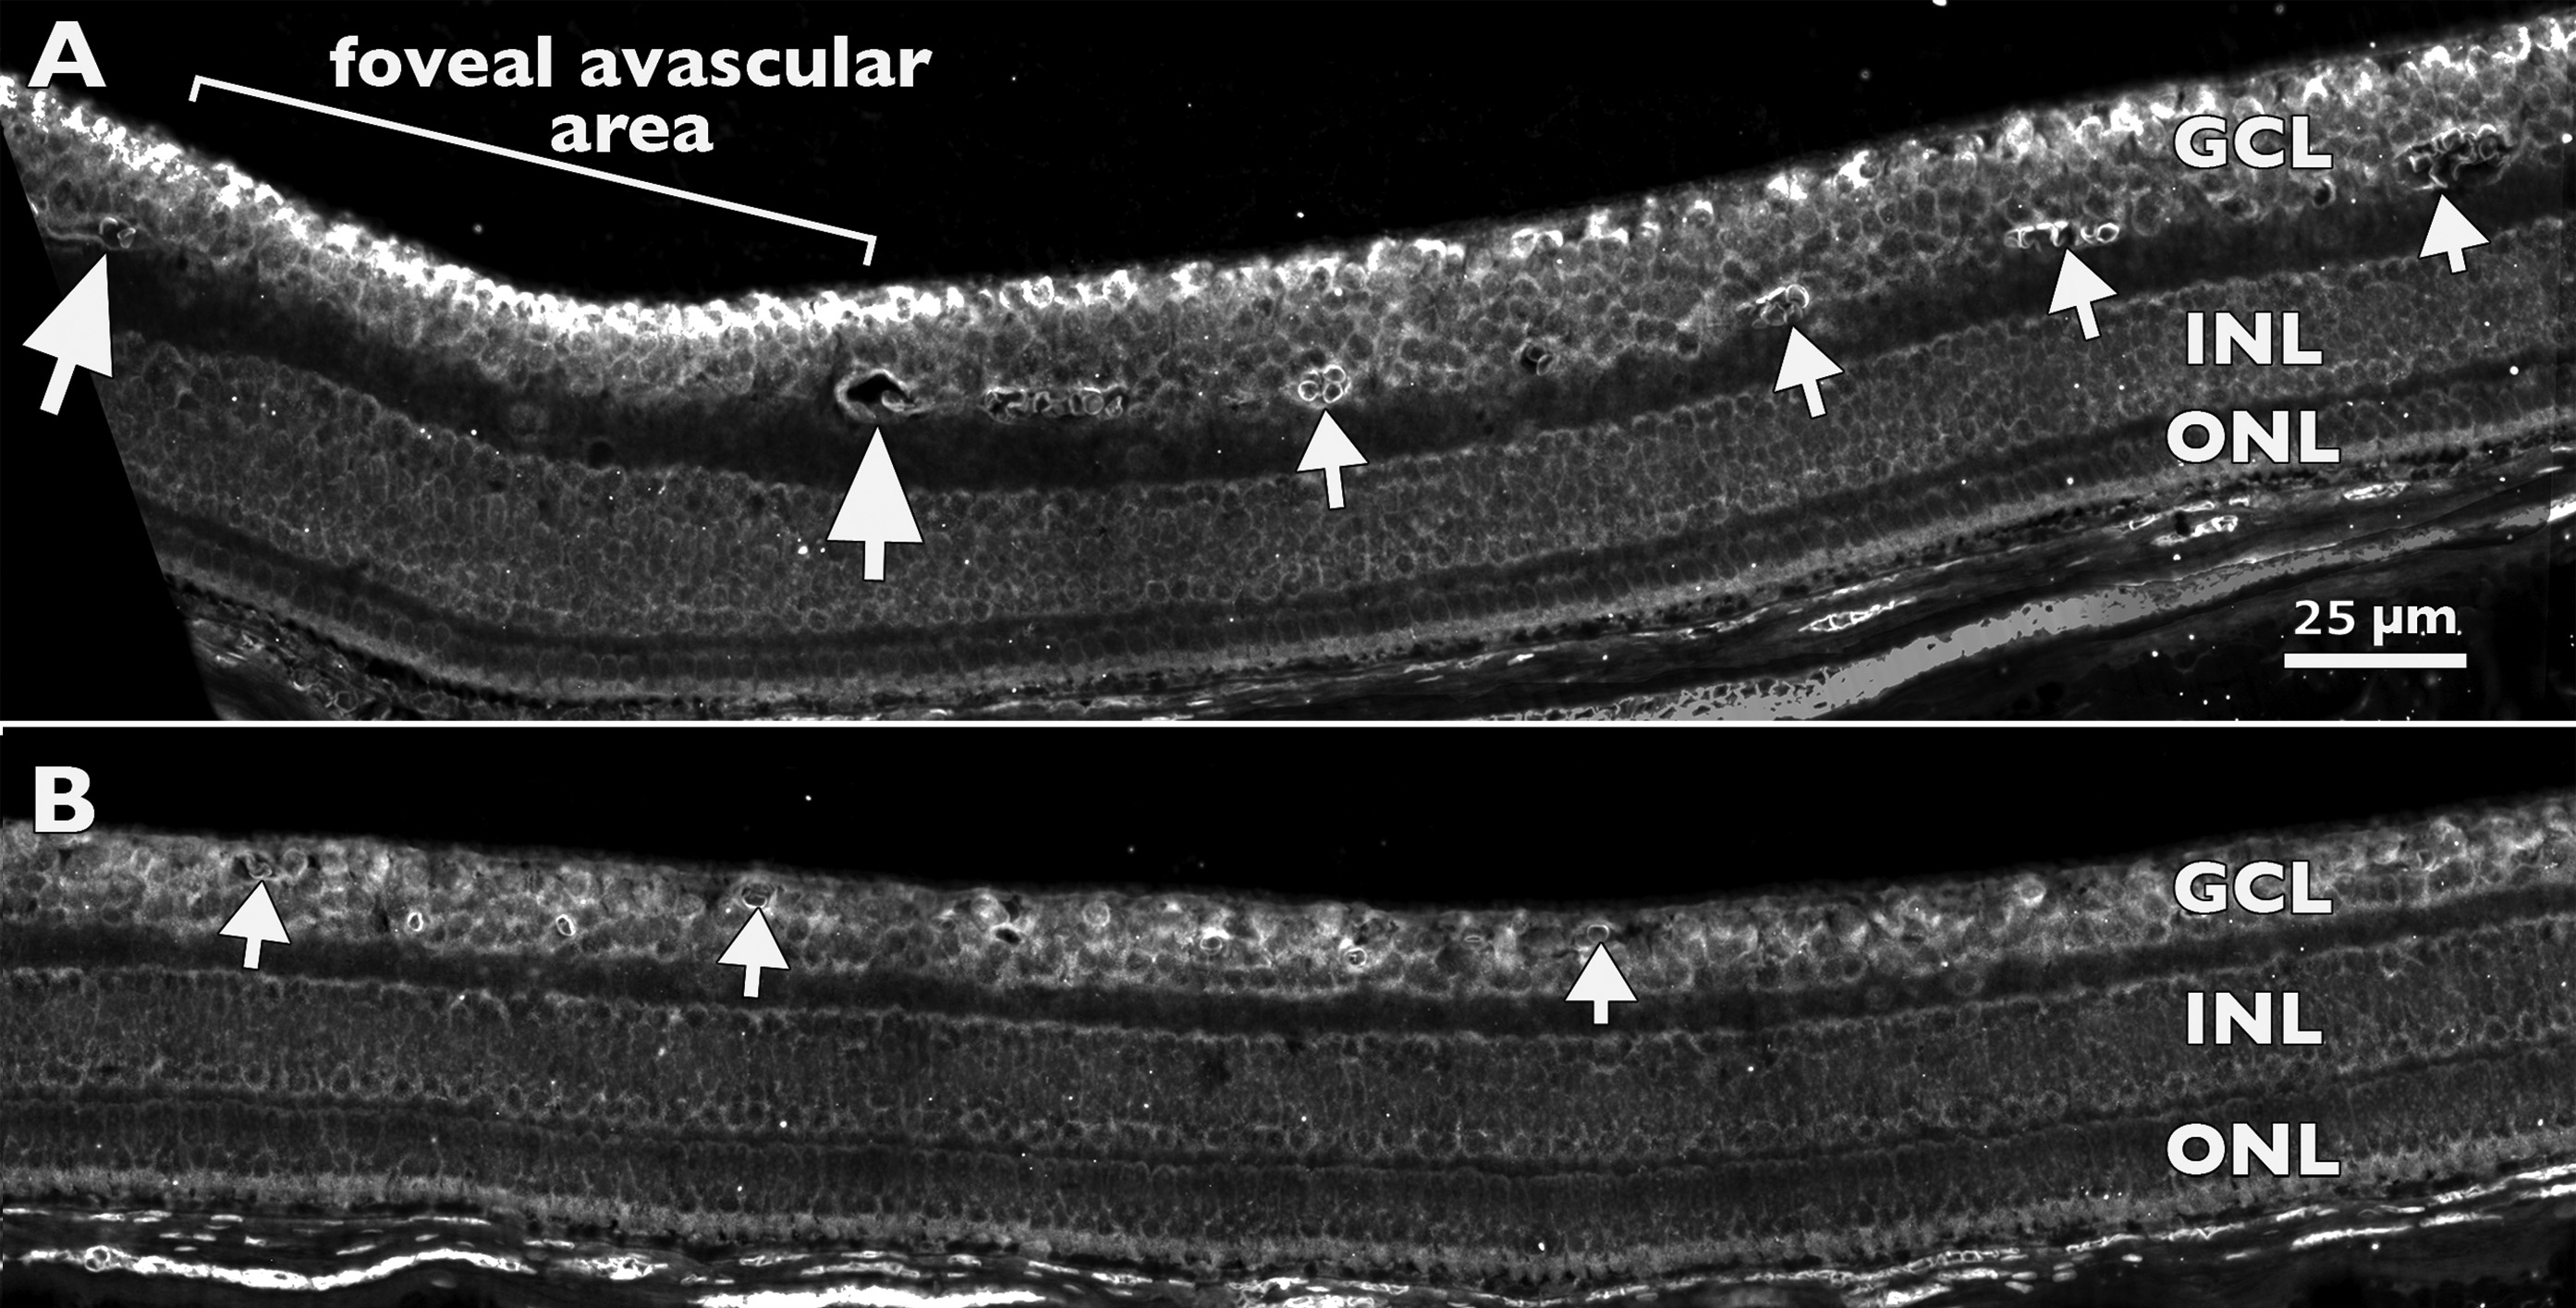

Figure 4. In situ hybridization for Eph-A6

expression in a Fd 115 macaque retina. A: At the developing

fovea and in adjacent temporal retina, peak Eph-A6 mRNA

expression is detected in the inner ganglion cell layer (GCL) within

the foveal avascular area (bracket). Large arrows mark vessels at the

inner margin of the perifoveal plexus. The area between the two large

arrows is devoid of vessels. Smaller arrows indicate vessel profiles

deep in the GCL (GCL plexus), which is a characteristic of macular

vessels. B: Approximately 500 µm further into temporal retina,

vessels (arrows) are present in the inner and outer GCL, and levels of Eph-A6

mRNA in the GCL are lower, and more uniform across the depth of the

GCL, compared with A. Together, the images show two gradients

of Eph-A6 expression: a high-to-low gradient from inner to

outer GCL at the developing fovea (in A), and a high-to-low

gradient from fovea to periphery (top left GCL in A to lower

right GCL in B). Both A and B are at the same

magnification. Abbreviations: inner nuclear layer (INL); outer nuclear

layer (ONL).